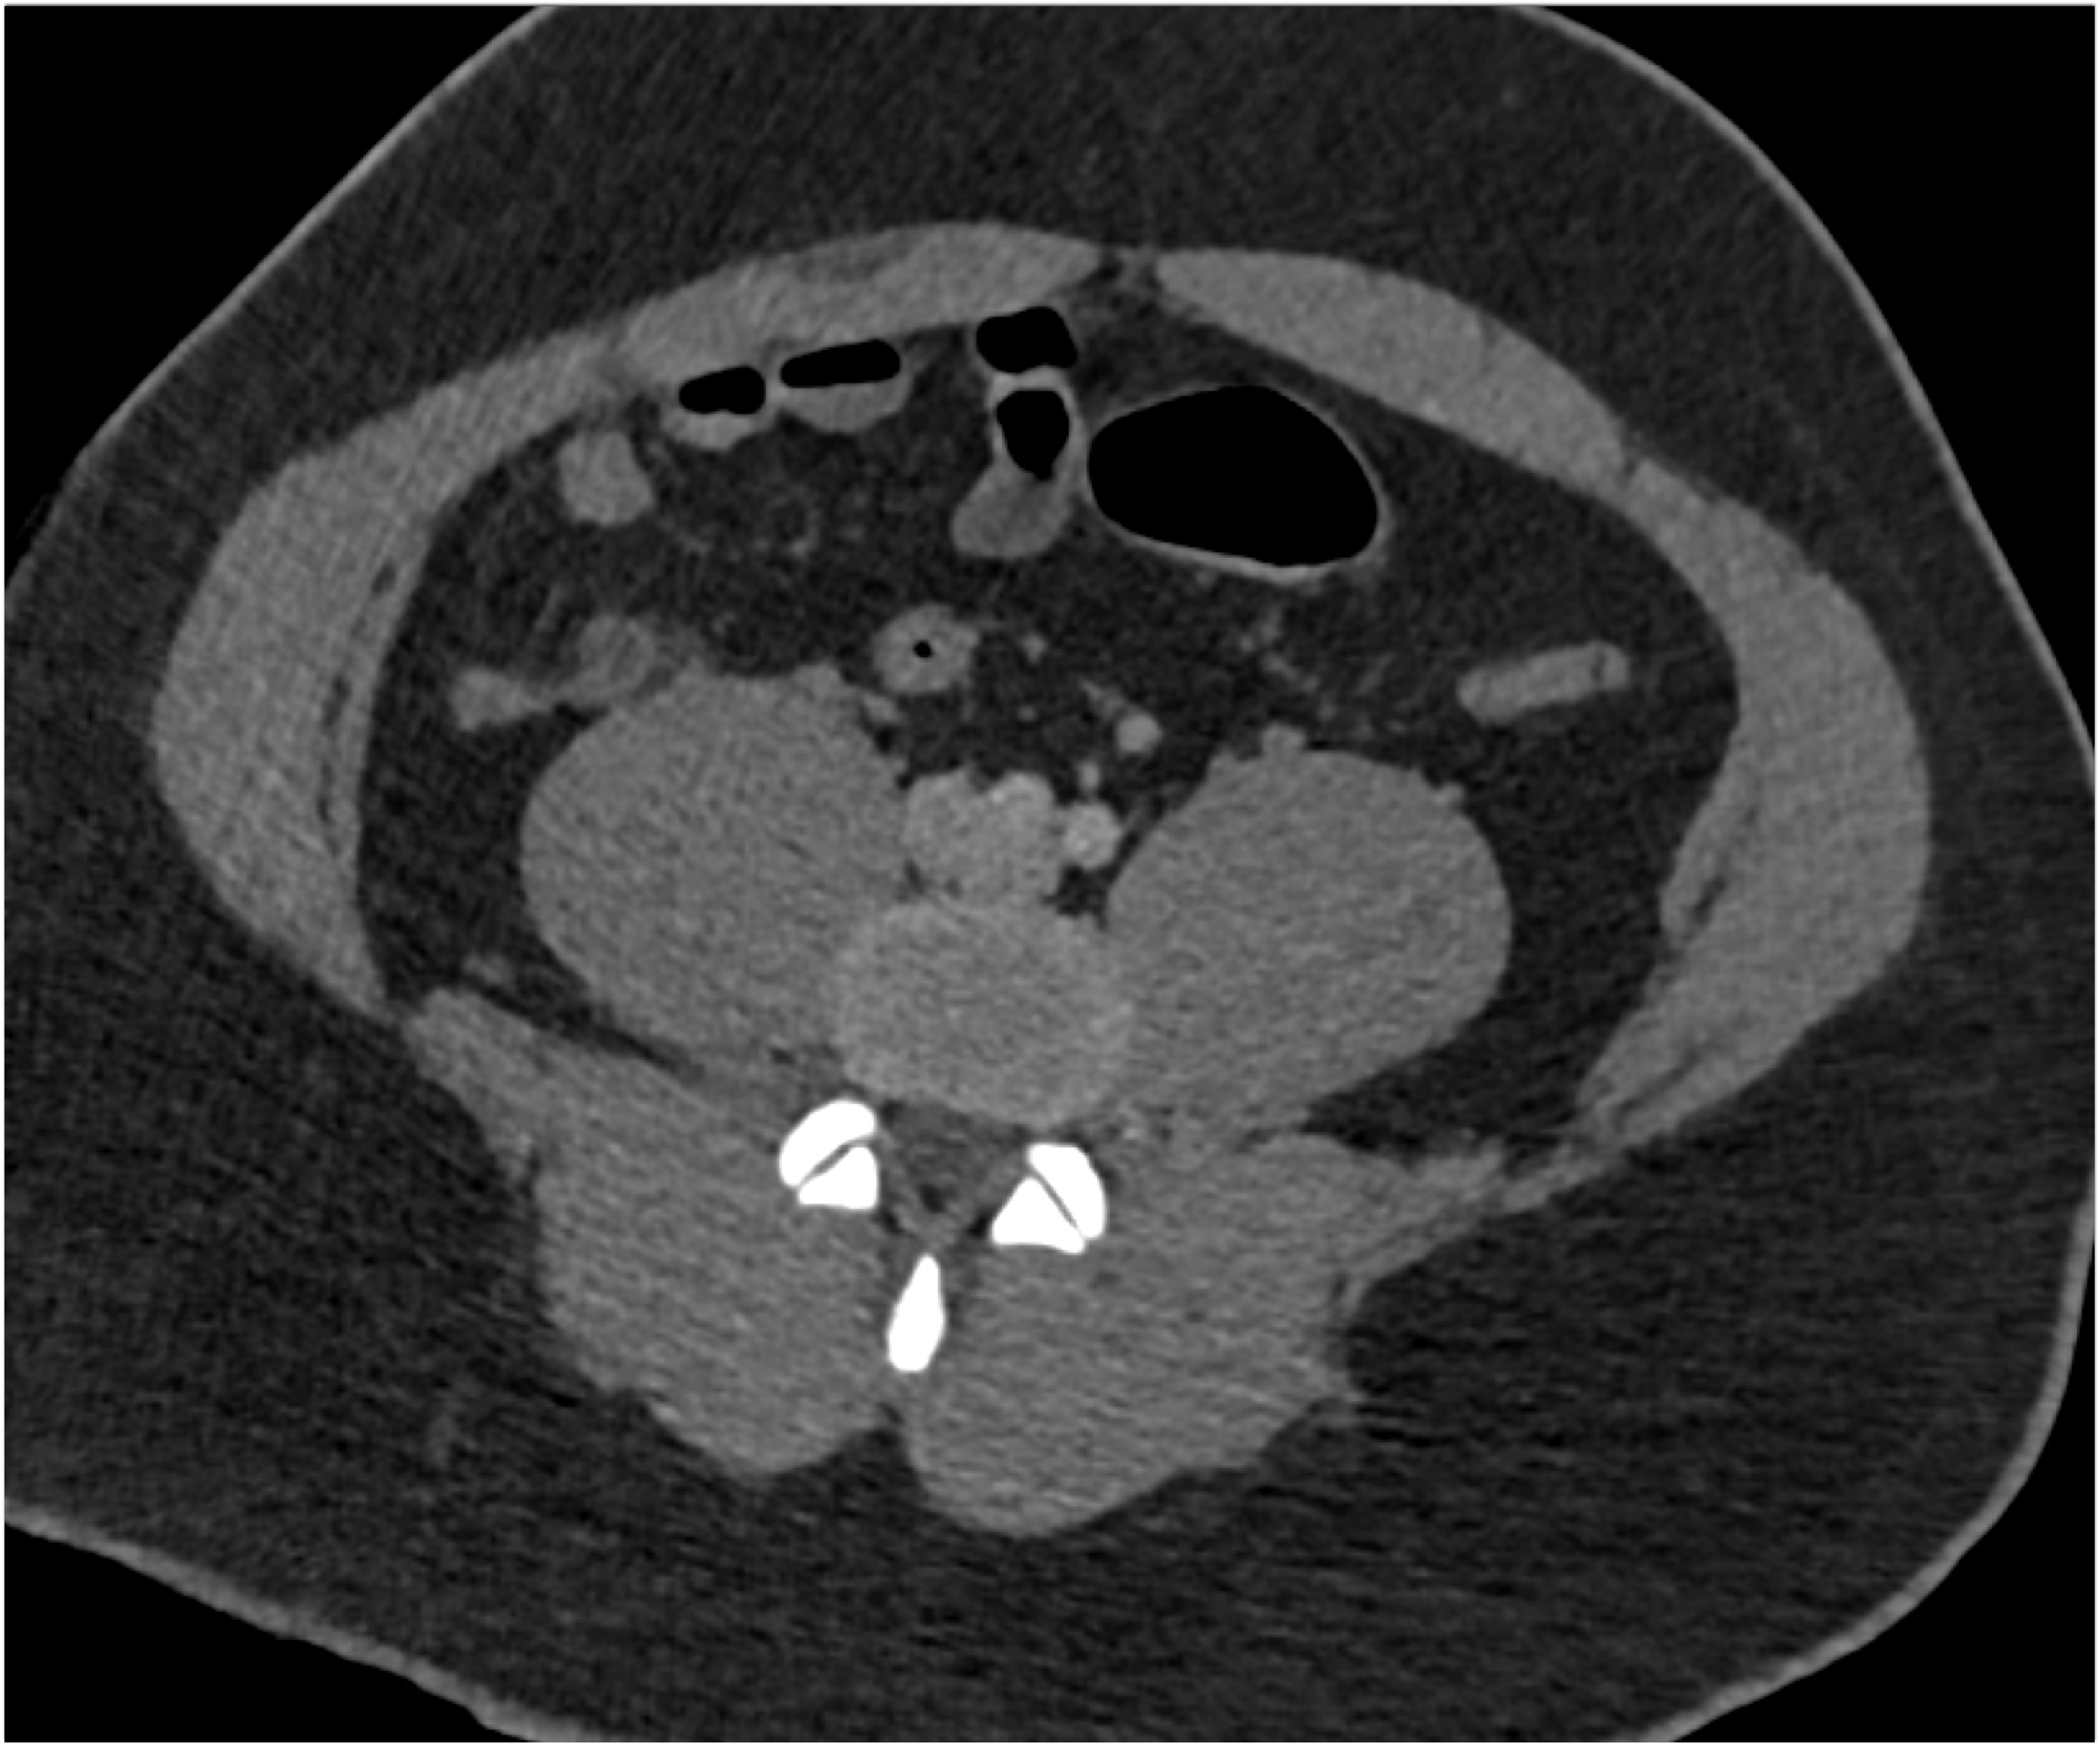

6) The most likely diagnosis in this 30ish year old is?

Meckel’s diverticulum

cecal diverticuli

acute appendicitis

ileal diverticulitis